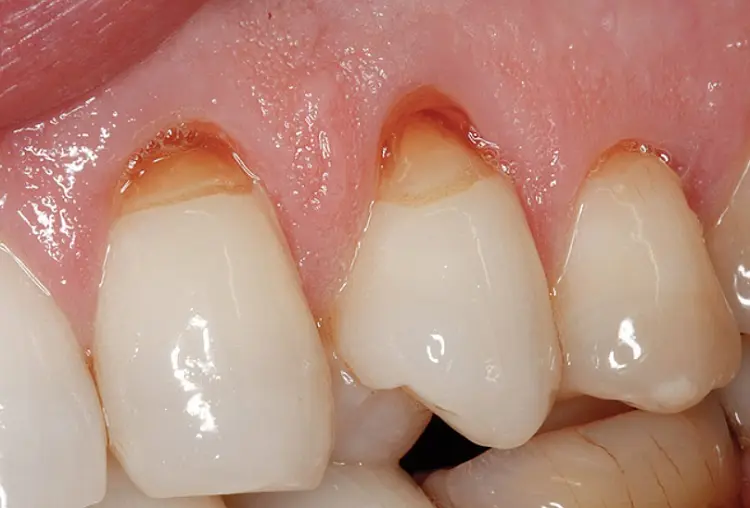

- Abrasi Servikal

Abrasi yang terjadi di area leher gigi, yaitu perbatasan antara gigi dan gusi. Kondisi ini membuat bagian tersebut tampak cekung atau terkikis. Biasanya disebabkan oleh kebiasaan menyikat gigi terlalu keras atau teknik menyikat yang kurang tepat.